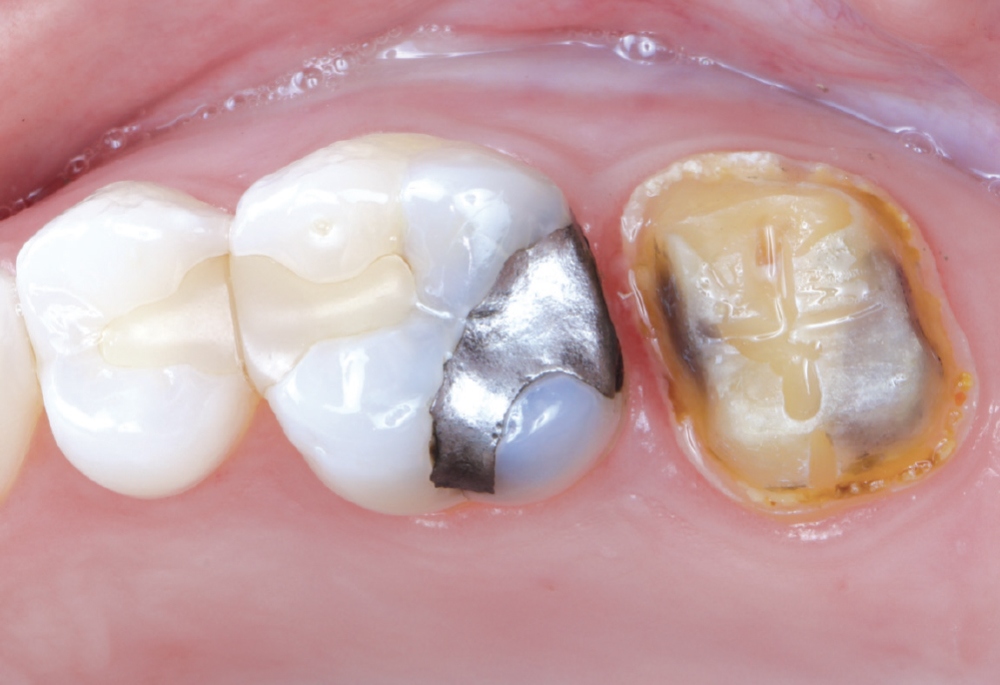

Even though she is a dental hygienist, Nikole decided to wait it out when she was told her crown on tooth #15 had an open margin. But over time, she noticed the area started to shred her floss. That’s when she decided it was time for the crown to be replaced.

Because the patient had high expectations for her restoration, I selected a BruxZir® Esthetic NOW Posterior Milling Block for its combination of esthetics and strength. Though BruxZir Esthetic was originally developed with the anterior in mind, with a yttria content that enhances the overall translucency and color, the material still maintains an excellent flexural strength of 870 MPa, meaning it is sufficiently strong enough to be used anywhere in the arch.

I enjoy using the glidewell.io system because I can provide a high-quality, same-day restoration. I’m in control of the contacts, shape, color and fit. The crown fits with minimal adjustments needed.

This was Nikole’s first experience with same-day dentistry, and she summed it up best: “I’m a fan! The new crown fit perfectly, with no return visit, no second round of anesthesia and barely any adjustments. The contacts are spot on, and flossing feels smooth.”